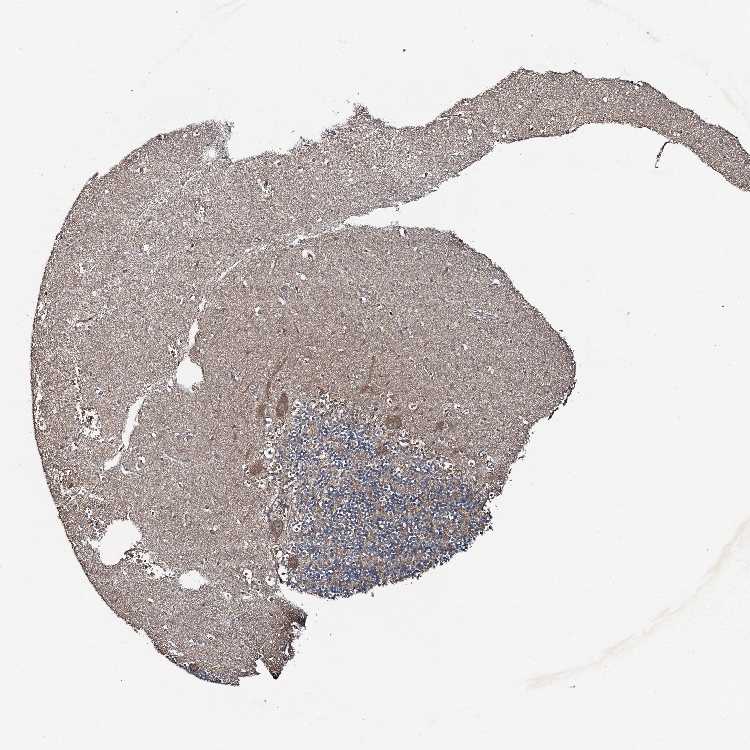

CEREBELLUM - Antibody stainingi

Antibody staining in the annotated cell types in the current human tissue is reported as not detected, low, medium, or high, based on conventional immunohistochemistry profiling in selected tissues. This score is based on the combination of the staining intensity and fraction of stained cells.

Each image is clickable and will lead to virtual microscopy that enables deeper exploration of all samples and also displays staining intensity scores, fraction scores and subcellular localization as well as patient and tissue information for each sample.

Antibody HPA041775

Purkinje cells Medium

Cells in granular layer Low

Cells in molecular layer Medium